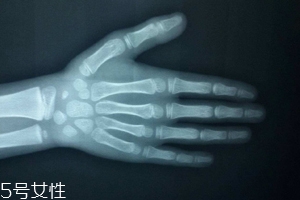

人的生長發(fā)育可用兩個(gè)“年齡”來表示,即生活年齡(日歷年齡)和生物學(xué)年齡(骨齡)。通過測定骨骼的大小、形態(tài)、結(jié)構(gòu)和相互關(guān)系的變化反映體格發(fā)育程度,并通過統(tǒng)計(jì)處理,以年齡的形式,以歲為單位進(jìn)行表達(dá)的生物學(xué)年齡。

只需要拍一張左手正位片。

拍攝時(shí),左手五指自然張開,手心向下,中指與前臂保持中一條直線(盡量不要左右偏,手臂放平不要上抬),X線球管對準(zhǔn)第三掌骨頭,球管與X光片距離在80CM左右。